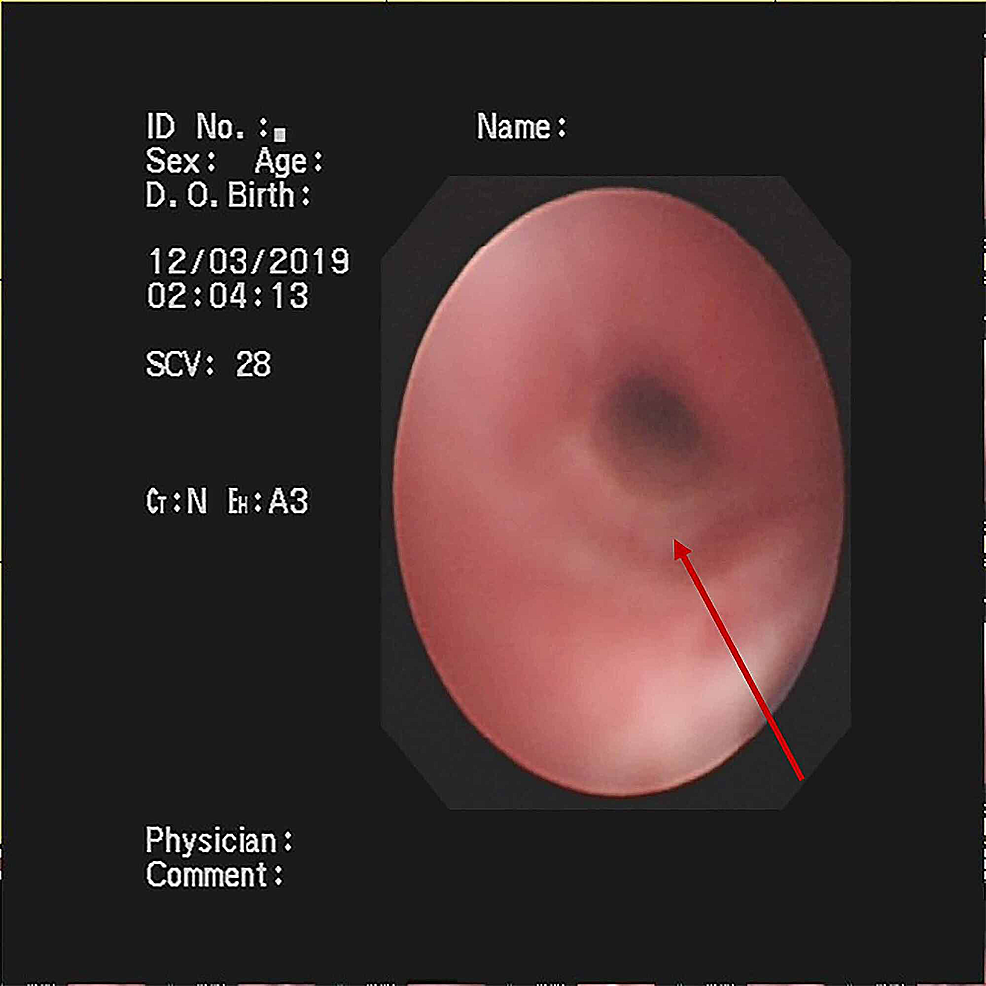

A previously healthy eight-year-old boy, without the history of wheezing and foreign body inhalation, was transferred to the emergency center of Jiangxi Provincial Children's Hospital from a basic-level hospital with a two-day history of fever, cough, and progressive dyspnea. His body temperature was approximately 38 °C. He had been previously treated with antibiotics at a local hospital without improvement except the normalized body temperature. Subsequently, he underwent chest computed tomography (CT) scans, which revealed atelectasis in the left lung and a foreign body in the left upper bronchus, along with pneumonia in the right lung (Figure 1A). In our emergency department, physical examination showed clouding of consciousness, cyanosis, rales, and diminished breath sounds in both lungs. Other parameters were as follows: body temperature, 36.9 °C; heart rate, 150 beats/minute; respiratory rate, 46 breaths/minutes; percutaneous oxygen saturation, approximately 70% under high-flow oxygen therapy. Since the local chest CT scan and clinical manifestations indicated a high possibility of foreign body inhalation, urgent bronchoscopy was performed. This procedure did not reveal the presence of any foreign body in the trachea of this patient but showed the presence of white gelatinous secretions that completely blocked the left main bronchus. Upon removal, it was observed that the secretions are shaped like a bronchial tree (Figure 2A). However, after this cast removal followed by bronchial lavage, there was no significant improvement in oxygen saturation, which fluctuated between 70% and 80%. The patient was admitted to the pediatric intensive care unit and intubated immediately.

After the observation of the cast that was removed via bronchoscopy, PB diagnosis was confirmed. Further, histopathology indicated that the casts predominantly comprised of inflammatory necrotic tissue, mucin, numerous neutrophils, and eosinophils (Figure 2C). Chest X-ray revealed pneumonia in both lung lobes and atelectasis in the left lung (Figure 1B), suggesting airway blockage by residual casts. Furthermore, complete blood count revealed the following: white blood cells, 13.11×109 cells/L (leukocytosis); neutrophils, 85.4%; hemoglobin, 145 g/L; and platelets, 350×1012/L. The blood biochemistry results of this patient were as follows: C-reactive protein (CRP), 42.6 mg/L; IgE, 908.4 IU/ml; IgA, 1.04 IU/ml; IgM, 0.62 IU/ml; and IgG, 12.15 IU/ml. As PB diagnosis is confirmed, along with extensive inflammatory necrotic tissue in the casts, we started treatments as follows: imipenem-cilastatin sodium (30 mg/kg, q6h) for anti-infection; azithromycin (10 mg/kg, qd); intravenous methylprednisolone (1 mg/kg, q12h); nebulized dexamethasone (5 mg, q6h) for anti-inflammation; nebulized bronchodilators, intensive chest physiotherapy, and intravenous mucosolvan for mucolytic therapy. However, oxygen saturation still fluctuated at approximately 80% without improvement for the next two days. Sputum etiology examination was positive for influenza A virus and negative for other viruses and Mycoplasma pneumoniae RNA, as well as fungi and bacteria. Additionally, blood cultures for bacteria and fungi were also negative.

Treatment regimens were adjusted based on the etiological results. Imipenem-cilastatin sodium and vancomycin were discontinued; further, the patient was administered with piperacillin (50 mg/kg, bid), and added Oseltamivir for anti-influenza A virus. Azithromycin (10 mg/kg, qd), intravenous methylprednisolone (1 mg/kg, q12h), nebulized dexamethasone (5 mg, q6h), nebulized bronchodilators, intensive chest physiotherapy, and intravenous mucosolvan were continued. However, there was still no improvement. Considering the histopathology showed the casts predominantly comprised of mucin, and the mucolytic agent mucosolvan, as well as bronchodilators, were not effective, we used a mucolytic agent-α-chymotrypsin, which has been reported to liquefy the mucus. α-chymotrypsin (2000 IU, 5 mL saline) was intratracheally instilled twice a day via the endotracheal tube, supplemented by frequent intratracheal suction and chest physiotherapy. Consequently, abundant purulent secretions and casts were discharged (Figure 2B); further, the oxygen saturation increased to 93% and there were enhanced breath sounds in both lungs. The patient was successfully extubated with gradual improvement in his condition. Subsequently, the patient received oral azithromycin (10 mg/kg, three times per week) and nebulized budesonide (1 mg added in 2 mL saline, twice daily). Chest CT reexamination showed the full expansion of the left lung with pleural effusion on the left thorax and bilateral pneumonia (Figure 3A). Additionally, fiberoptic bronchoscopy revealed endobronchial intima infection without casts (Figure 4). After six days, he was discharged with a little cough and no neurological sequelae; continued on oral azithromycin and nebulized budesonide treatment for two weeks. The timeline of this case was shown in Figure 5. During the next four follow-up visits, the patient was asymptomatic and without recurrent casts. Further, his chest CT scan showed increased lung markings (Figure 3B).